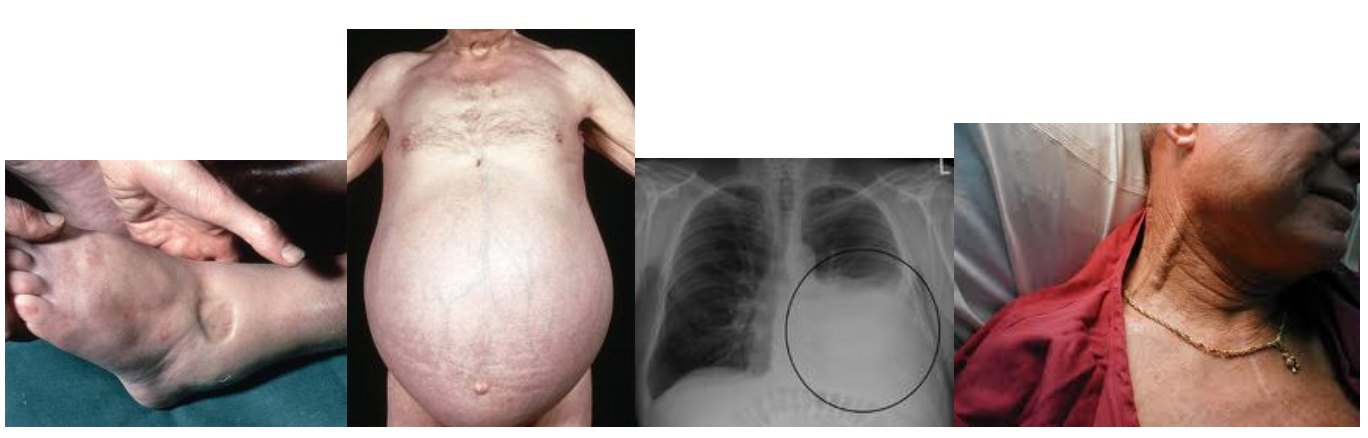

- ការហើមនៅចុងអវៈយវៈផ្នែកខាងក្រោម (peripheral edema)

- ថ្លើមរីកធំ (hepatomegaly) អណ្តើករីកធំ (spleenomegaly)

- ទាចទឹក (ascites)

- ទឹកនៅចន្លោះស្រោមសួត (pleural effusion)

- ប៉ោងសរសៃឈាមវែននៅ ក (distended jugular veins)

ការពិនិត្យរាងកាយអ្នកជំងឺ គឺចាំបាច់រួមបញ្ចូលទាំងសញ្ញាតំអូញដែលបានបញ្ជាក់រួចមកហើយមានដូចជាការហើមនៅចុងអវៈយវៈផ្នែកខាងក្រោម (peripheral edema) និងប៉ោងសរសៃ វ៉ែននៅ ក (distented jugular veins)។